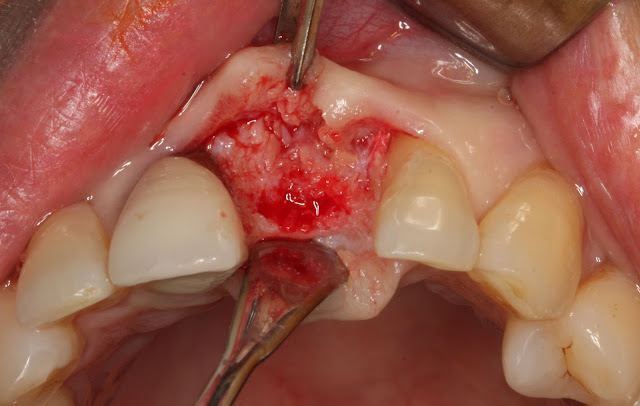

Due to chronic periodontitis in tooth number 21, immediate implant placement was not possible. Therefore, extraction was performed first, followed by socket preservation after the extraction.

The infected tissue inside was meticulously removed, dedicating time to ensure thorough removal.